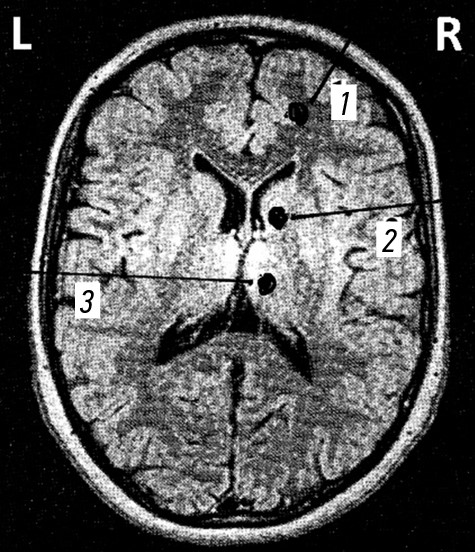

С опорой на данные табл. 4, структуры ГМ (по данным магнитно-резонансной томографии) были условно разделены на две анатомические зоны (рис. 1).

Рис. 1. Условное разделение головного мозга на зоны: a — сагиттальный срез; b — аксиальный срез. 1 — подкорковые образования, желудочки и ствол головного мозга; 2 — кора головного мозга и полушария мозжечка.